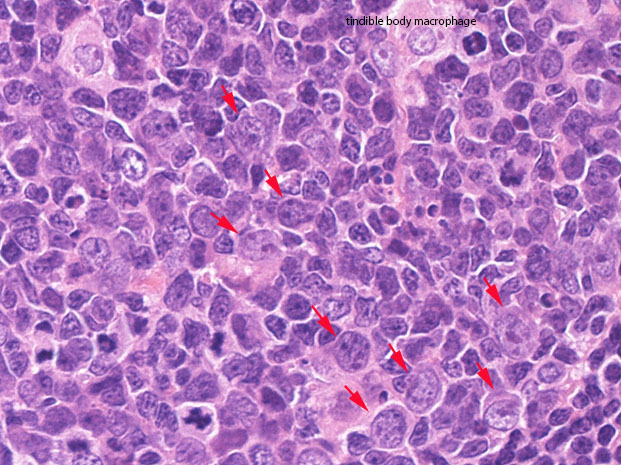

germinal center(GC)は, B細胞, T細胞, 抗原提示細胞, tindible-body macrophageが混在して構成されている. B細胞が優位に多く, small/ large cleaved cell(centrocytes)とlarge non-cleaved cells(centroblasts)が認められる。

胚中心内で, 明るい類円形の核が2つくっついている細胞はまずtindible body macrophage follicular dendritic cellでtindible body macrophageとの鑑別に有用です. (竹内賢吾Dr談)

高度に活性化された胚中心では, centrocyteとT細胞から構成される light zone (LZ)と増殖の盛んなcentroblastsとtindible-body macrophageの多いdark zone(DZ)が区分されるようになり, 極性(polarization)をもつといわれる.

centrocytes(左図), centroblasts(中央, 赤矢印), Mantle zone-GC boder(右図) クリックで拡大図.

centroblastは類円形大型のvesicularな核をもったN/C比大の細胞. 核小体が複数個核辺縁にくっつくように認められる. 胚中心には核分裂像やapoptosis像が多く, 正常胚中心のMIB-1 indexは高い。(FLでは low MIB-1 indexとなる. 後述)